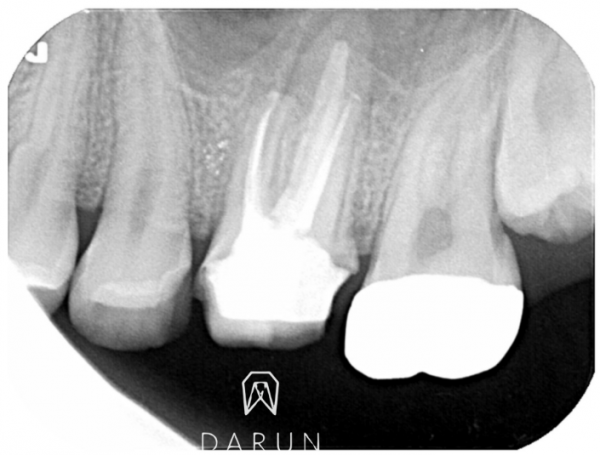

청소 후 모습입니다. 아주 많이 좋아졌어요.

이제 치료 마무리 준비중입니다~

한 근관 오염이 너무 심해서,

일반적으로 쓰는 Gutta percha 재료만으론 한계가 있어서,

여러종류 의 MTA를 함께 이용했습니다.

오염된 부분들이 eradicate 이면 좋겠지만,

잘 정리되었단 사인도 보이네요

Are we there yet? 이라고 외치던 친구..

고생했어요. 정말. 오랫동안 쓰길 바래요!